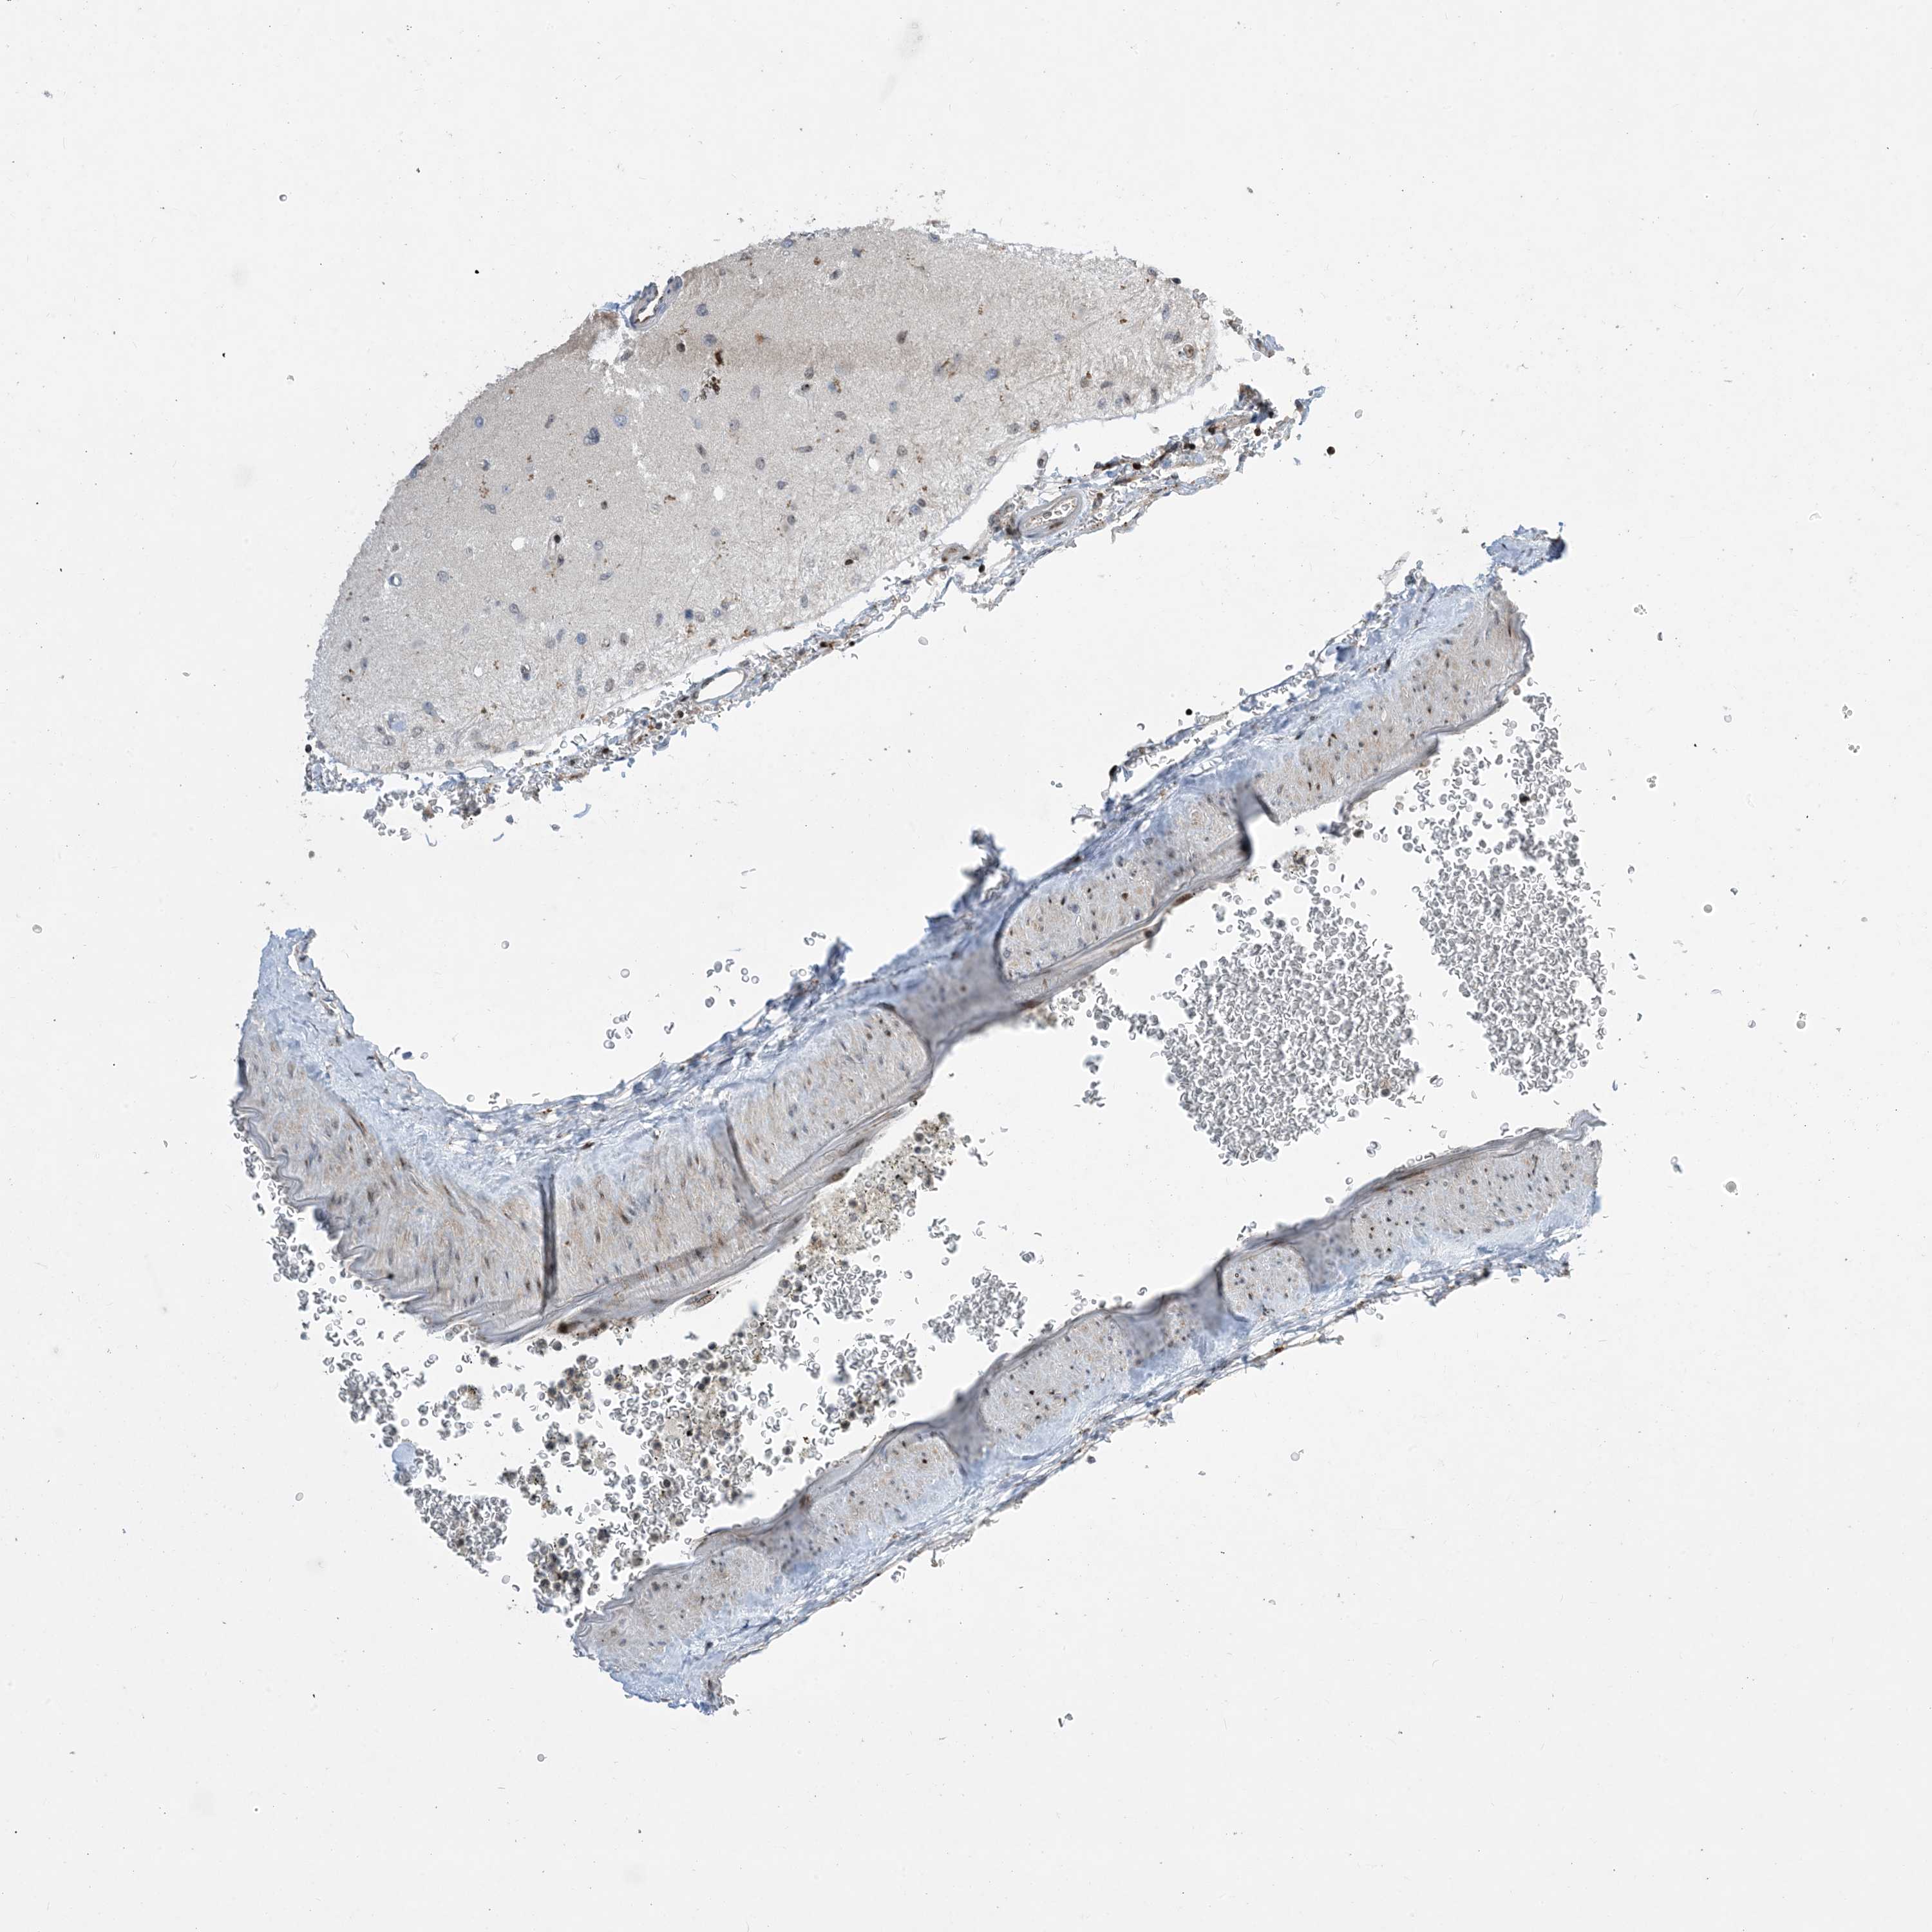

GLIOMA - Protein expressioni

A mouse-over function shows sample information and annotation data. Click on an image to view it in a full screen mode. Samples can be filtered based on level of antibody staining by selecting one or several of the following categories: high, medium, low and not detected. The assay and annotation is described here.

Note that samples used for immunohistochemistry by the Human Protein Atlas do not correspond to samples in the TCGA dataset.

Antibody stainingi

Antibody staining in the annotated cell types in the current human tissue is reported as not detected, low, medium, or high, based on conventional immunohistochemistry profiling in selected tissues. This score is based on the combination of the staining intensity and fraction of stained cells.

Each image is clickable and will lead to virtual microscopy that enables deeper exploration of all samples and also displays staining intensity scores, fraction scores and subcellular localization as well as patient and tissue information for each sample.

Antibody HPA034959

Staining

High

Medium

Low

Not detected

Intensity

Strong

Moderate

Weak

Negative

Quantity

>75%

75%-25%

<25%

None

Location

Nuclear

Cytoplasmic/membranous

Cytoplasmic/membranous,nuclear

Glioma, malignant, High grade

Glioma, malignant, Low grade

Glioblastoma, NOS